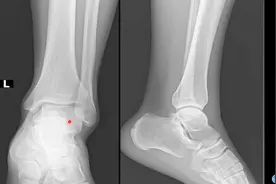

人体局部解剖学-踝关节解剖

影像基础知识:踝关节骨解剖讲解,简单易懂,3分钟学会

★踝关节解剖收藏图谱MR(活到老,学到老!)普通人也能看懂!

踝关节是人体负重的主要关节之一。 在负重中期,踝关节关节面承受的压力约为体重的两倍,在负重后期则可以高达到体...

踝关节MRI解剖及7种常见损伤类型